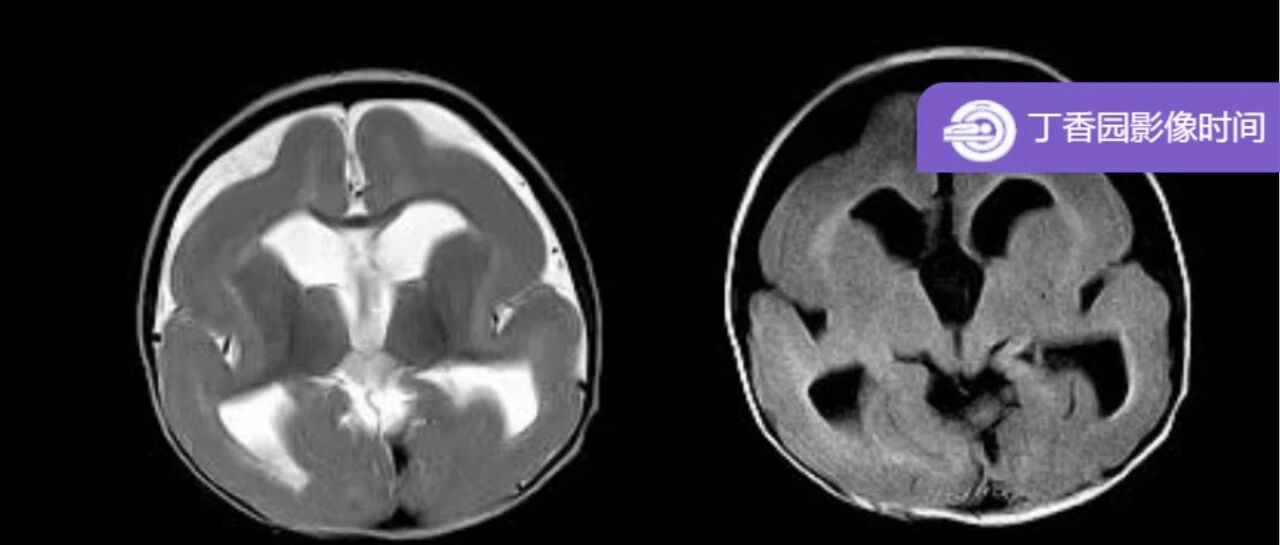

先天性颅脑发育异常和家族性疾病 丁香园影像时间 · 公众号 · 医学 · 1 年前 · |